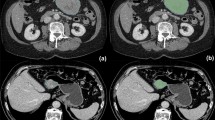

Tumor segmentation

Lesions were delineated on the CT arterial phase images using the ITK-SNAP software (available at www.itk-snap.org), because the arterial phase is better for distinguishing a tumor mass from adjoining normal tissue. The whole-tumor volume was determined by manually drawing a region of interest along the border of the tumor on each consecutive slice covering the whole lesion while excluding intra-luminal air and calcification. Two experienced radiologists, both with least 10 years of abdominal imaging experience and blind to the clinical outcomes, conducted the process in consensus. Therefore, a three-dimensional (3D) volume of interest (VOI) was finally obtained (Fig. 2).